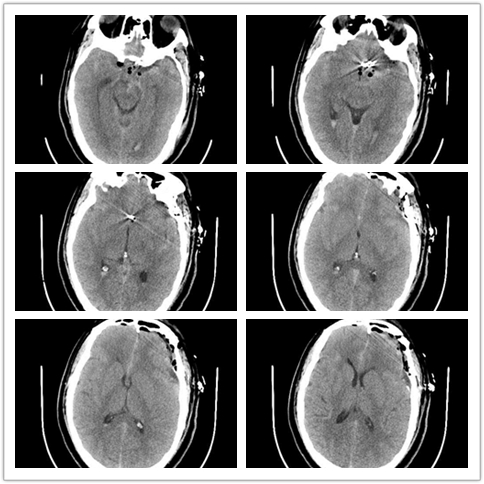

术后复查

术后视频:术后2周余出院,详见下方术后康复视频。